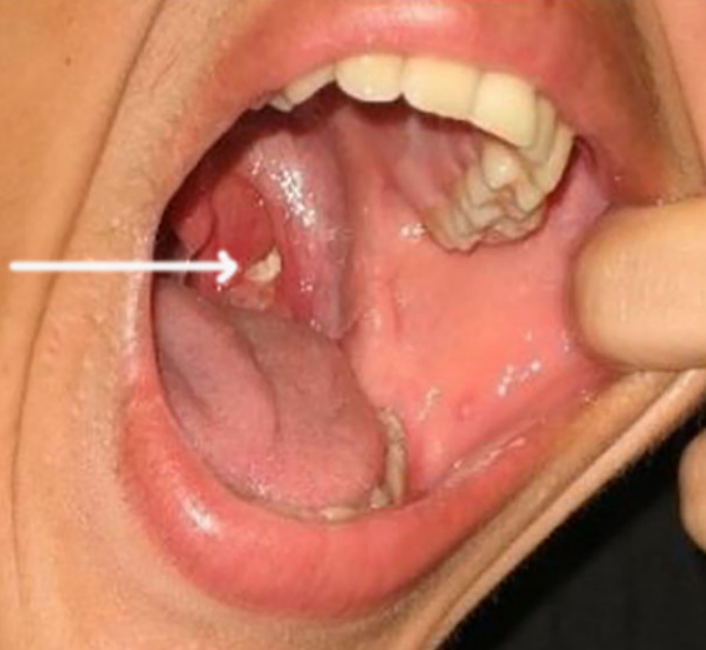

편도결석은 편도 주변에 생기는 결석을 말하는데 편도나 편도선에 있는 작은 구멍인 편도와에 노란 알갱이의 형태로 쌓이는 것을 편도결석이라고 부릅니다. 편도결석은 입안에 남아있는 음식물 찌꺼기와 각종 세균이 뭉쳐서 생기는 것으로 편도결석의 원인이 되는 불결한 구강상태는 편도결석으로 인한 입냄새를 생기게 할 수 있습니다.

편도결석은 결석이라고 해서 돌과 같이 딱딱한 형태는 아니지만 쌀알 크기의 작고 노란 형태로 생깁니다. 편도결석의 주요 원인은 만성 편도염인데 만성 편도염에 걸리게 되면 편도나 편도선에 있는 작은 구멍인 편도와의 구멍이 넓어지게 됩니다.

3. 면봉

면봉을 사용하면 직접적으로 거울로 보면서 편도결석을 쉽게 제거할 수 있습니다. 거울을 보면서 제거할 때는 밝은 곳에서 하는 것이 효과적이며 편도결석이 있는 곳을 면봉으로 눌러주면 살살 긁어내면 노란 알갱이의 결석을 제거할 수 있습니다. 단, 무리하게 사용을 할 경우에는 구역질이 날 수도 있으며 편도에 상처가 생길 수도 있으니 주의하는 것이 좋습니다.